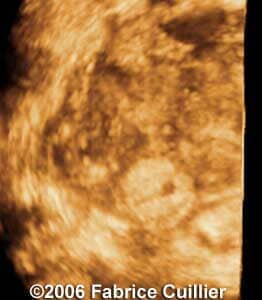

These are some cases of ectopic pregnancy (GEU) using the 2D and 3D scans.

Case 2